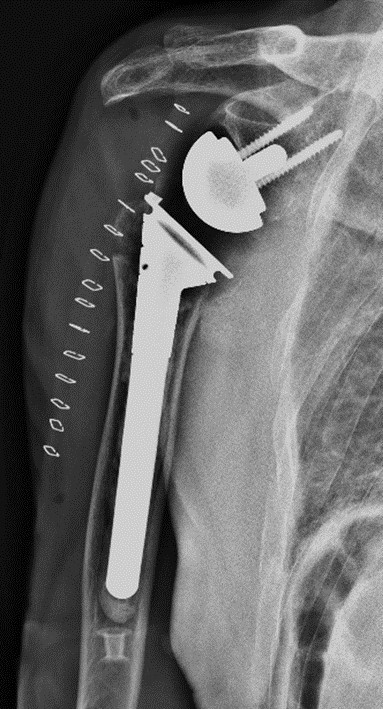

术后复查X线片示关节假体位置良好

在麻醉手术科、输血科等科室的全力配合下,王亮副主任医师团队顺利取出骨折块,精确处理大小结节,安装关节假体,重建了肩关节的稳定性,整个手术过程顺利。术后复查X线提示假体位置良好,关节对位满意。